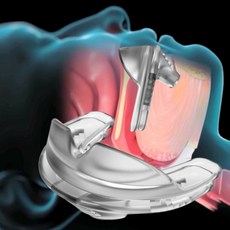

현재 코골이와 수면무호흡증에 대한 비수술 치료로는 양압기 치료가 세계적으로 권고되고 있다. 스페인 페셋박사대학병원 마리나 카라스코 야타스(Marina Carrasco-Llatas) 교수팀에 따르면, 폐쇄성수면무호흡증은 양압기 치료가 매우 효과적이다. 연구팀에 따르면, 상부기도를 열어 호흡 흐름을 원활하게 해주는…

양압기는 대부분의 수면무호흡증이나 코골이 개선에 많은 도움이 되는 장치다. 양압기는 일정한 압력으로 공기를 불어 넣어 상기도가 좁아지거나 닫히지 않도록 도와주는 의료기기다. 개개인의 상태에 가장 적합한 압력을 찾아 가동해야 치료 효과를 높일 수 있으므로 반드시 의료진과 상담하여 양압기 처방을…

수면무호흡증에 의한 수면의 질 저하는 양압기 사용이 일반적인 치료법이다. 양압기 치료는 상기도에 일정한 압력의 공기를 주입하여 수면 중 기도가 막히거나 좁아지는 것을 예방해주어 주간 졸림 등의 증상 개선과 더불어 심혈관 질환과 뇌혈관 질환의 치료에 중요한 역할을 한다. 대한수면호흡학회 교육이사인…

치료는 양압기 치료다. 기계에서 공기를 공급해 압력을 가하면 좁아지는 기도를 열어주고 폐를 펴주는 것과 함께 심장도 짜주는 효과를 낸다. 수면다원검사 결과 수면무호흡증을 진단받으면 보험 적용으로 월 2만 원 미만의 본인 부담금으로 치료를 받을 수 있다. 처음 양압기를 접하면 그 생김새와 평생 사용해야…

비수술적 치료이자 1차 치료법인 양압기 치료는 코에 공기를 불어넣고 기도 내 공기 압력을 높여 기도가 폐쇄되지 않도록 한다. 다만 양압기를 사용하지 않으면 수면무호흡증에 다시 노출되기에 매일 잠자는 동안 꾸준히 양압기를 착용하는 게 중요하다. 그런데 양압기 착용이 번거로워 적지 않은 환자(30~40%)가…

연구팀은 수면무호흡증 환자의 인지기능장애 치료는 그 방법에 따라 다양하지만, 지속적인 양압기 요법이 가장 효과적이라고 강조했다. 연구팀은… 현재 코골이나 수면무호흡증에 대한 일차치료에는 비수술법 요법인 양압기 치료가 권고되고 있다. 양압기는 안전하고 효과의 적용 범위가 넓으면서 부작용이…

비수술적 치료이자 1차 치료법인 양압기 치료는 코에 공기를 불어넣고 기도 내 공기 압력을 높여 기도가 폐쇄되지 않도록 하는 것이다. 미국 수면학회에서는 심혈관장애를 겪거나 고위험자에게는 1차적으로 양압기 치료를 권장한다. 양압기 전문 요원이 있는 병원에서 의사 조언에 따라 훈련해야 효과적으로…